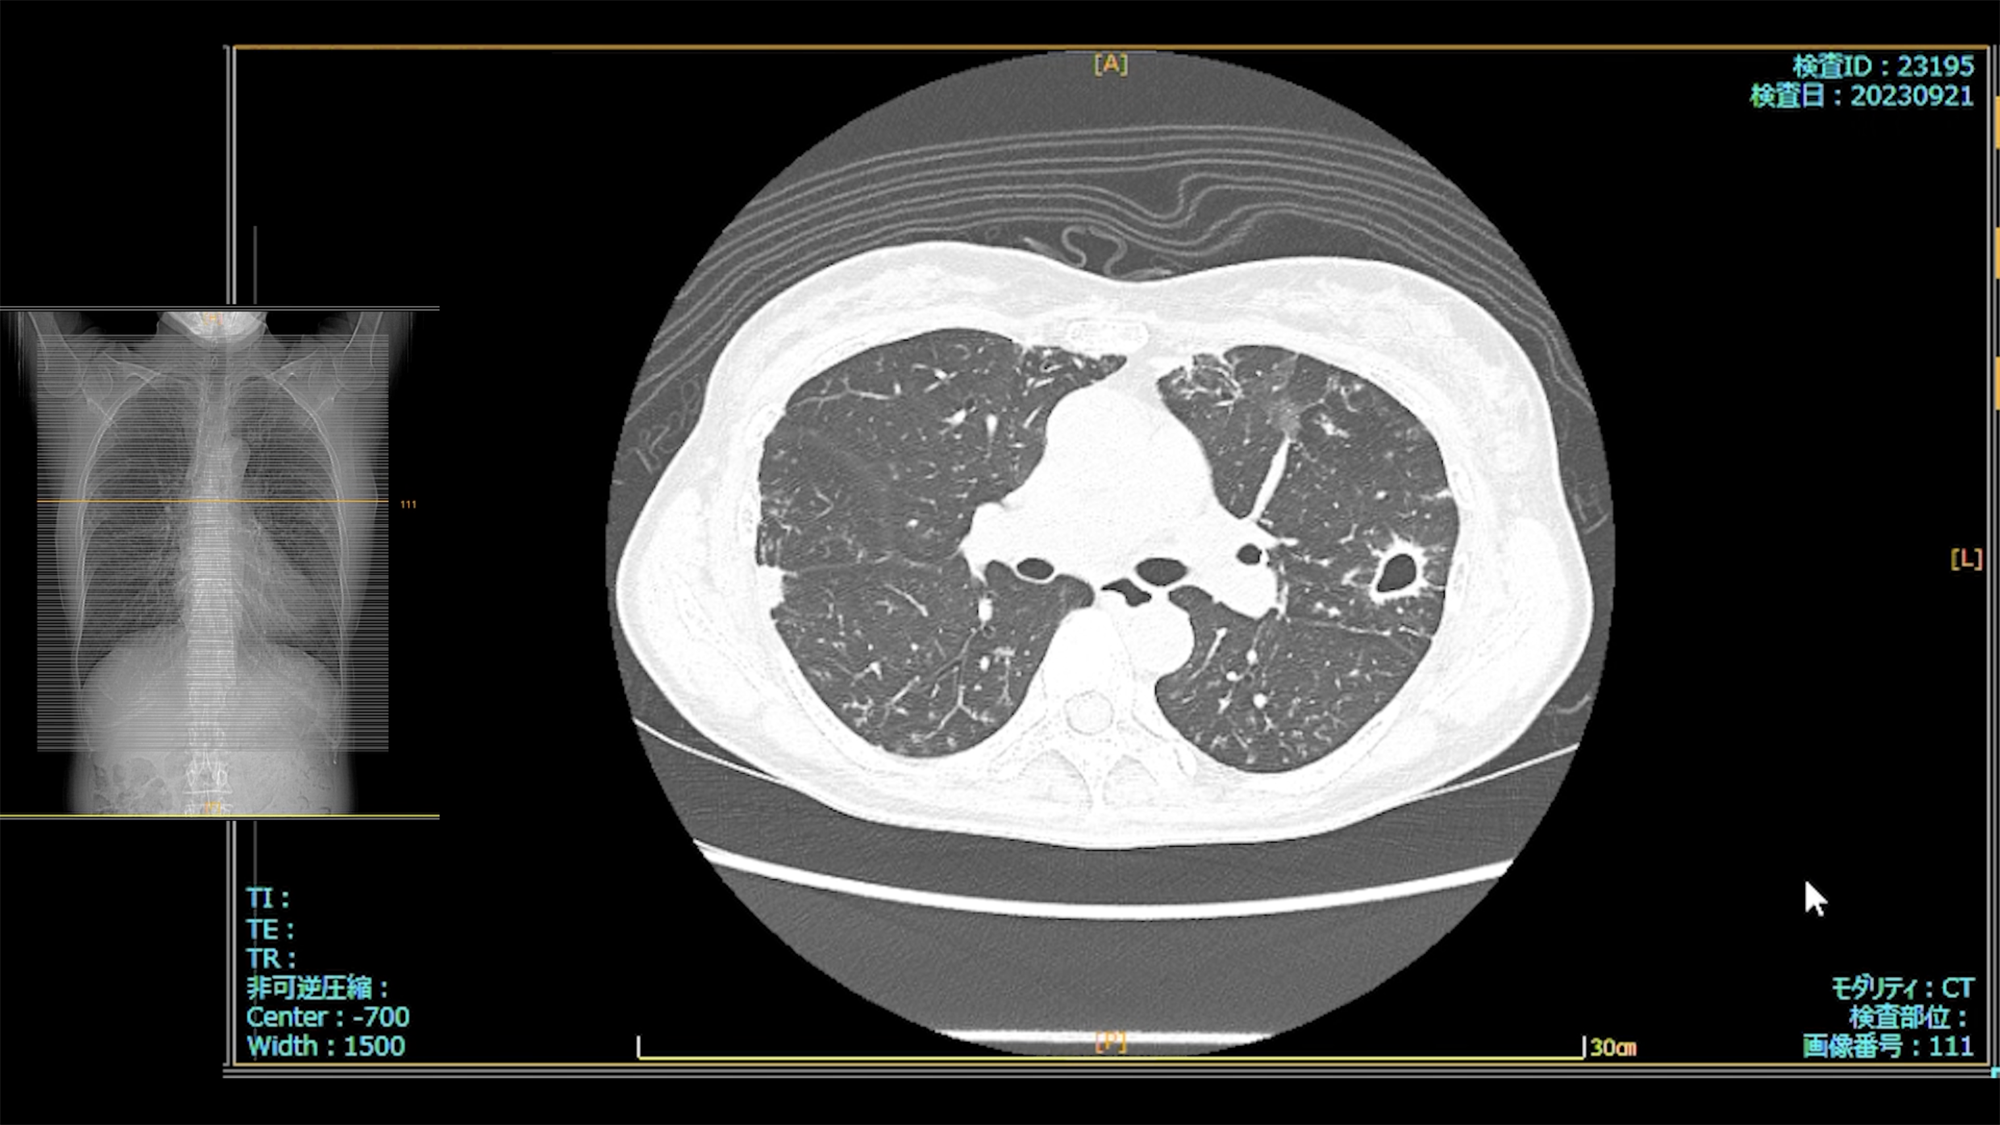

- 2023.09.21 入院加療の必要ありと診断された画像(国立系病院)